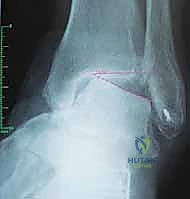

عملية تثبيت مفصل الكاحل والقدم الخلفية، والمعروفة طبياً بـ (Tibiotalocalcaneal Arthrodesis)، هي إجراء جراحي معقد يهدف إلى دمج (لحام) ثلاثة عظام رئيسية معاً لتكوين كتلة عظمية واحدة صلبة وغير متحركة. هذه العظام هي: عظمة الساق الكبرى (Tibia)، وعظمة الكاحل (Talus)، وعظمة الكعب (Calcaneus).

يتم هذا الدمج باستخدام مسمار نخاعي (Intramedullary Nail) طويل وقوي يُدخل من أسفل الكعب ليخترق العظام الثلاثة، ويتم تثبيته ببراغي قفلية لضمان أقصى درجات الثبات. الهدف من إلغاء الحركة في هذه المفاصل التالفة هو القضاء التام على الاحتكاك العظمي الذي يسبب الألم المبرح، مما يوفر للمريض قاعدة ثابتة وقوية للمشي.

يعتمد الدكتور هطيف على الأشعة السينية (X-rays) والأشعة المقطعية (CT Scans) ثلاثية الأبعاد لبناء خريطة دقيقة للتشوهات العظمية وتحديد حجم ومسار المسمار النخاعي المناسب لكل مريض بدقة متناهية. يتم مناقشة كل هذه التفاصيل بشفافية تامة مع المريض.